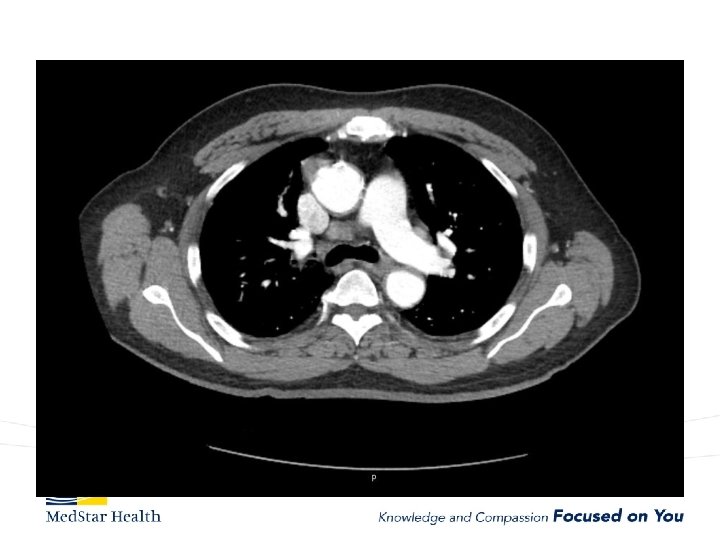

Acute Type B Aortic Dissection • Incidence: 2. 6 -3. 5 per 100, 000 patient-year • Uncomplicated • Complicated – – Malperfusion Rupture Unremitting Pain Uncontrolled HTN

Type B Dissection Complicated Uncomplicated Risk TEVAR age, comorbidities Extreme Low Medical Management False Lumen Small, Thrombosed Medical Management Patent/Large(>22 mm), Total Aorta >40 mm TEVAR/adjuncts